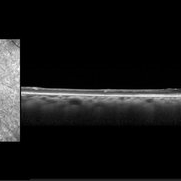

Branch retinal artery occlusion Branch retinal artery occlusionJan 24 2023 by Rayna Marshall OCT image of a 54-year-old female with an asymptomatic chronic branch retinal artery occlusion in the left eye showing inner retinal atrophy in the inferior macula corresponding to the region of chronic ischemia. Vision was 20/20. Photographer: Drew H. Scoles, MD, PhD, University of Pennsylvania Condition/keywords: branch retinal artery occlusion (BRAO), BRAO, embolus